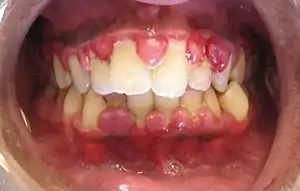

| Gingivitis, a common cause of inflammatory gingival enlargement. | |

Gingival enlargement has a multitude of causes. The most common is chronic inflammatory gingival enlargement, when the gingivae are soft and discolored. This is caused by tissue edema and infective cellular infiltration caused by prolonged exposure to bacterial plaque, and is treated with conventional periodontal treatment, such as scaling and root planing.[1]